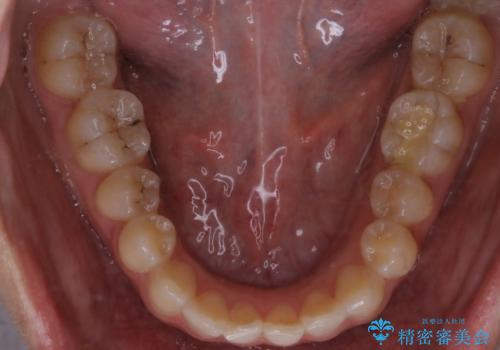

【非抜歯】部分矯正でも治る 前歯の反対咬合

- 前歯にガタつきを主訴にご来院されました。

奥歯の嚙み合わせに問題がほとんどみられなかったため、インビザライン ライトパッケージでの部分矯正を行うこととなりました。

今回のケースでは奥歯の噛み合わせに問題がほぼみられなかったため、前歯の位置のみに焦点を当て部分矯正を行いました。